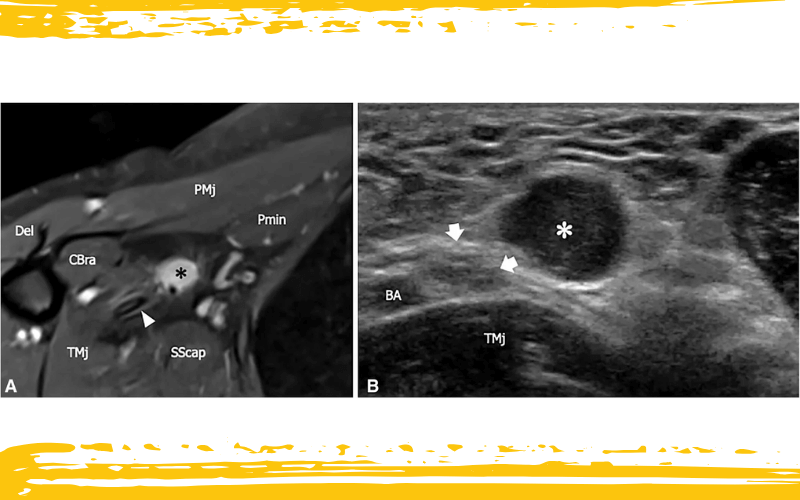

Schwannoma del nervio cutáneo medial del brazo en un paciente con dolor y parestesias en la cara interna del brazo distal.

En A, la imagen axial en secuencia STIR (Short-Tau Inversion Recovery) y en B la imagen ecográfica transversal muestran una masa (asterisco negro en A, asterisco blanco en B) originada en el nervio cutáneo medial del brazo a nivel de la axila. La lesión está en estrecha relación con el nervio cubital (flechas blancas en B) y con la arteria braquial (BA). La masa presenta márgenes regulares y bien definidos, aparece marcadamente hiperintensa en la secuencia ponderada en T2 y homogéneamente hipoecoica en la ecografía.

La hipótesis de schwannoma se confirmó posteriormente mediante análisis histológico. Tras la resección quirúrgica de la masa, el paciente refirió una clara mejoría de los síntomas, persistiendo únicamente una pequeña zona de hipoestesia residual a nivel del epicóndilo medial.

Del: deltoides; CBra: coracobraquial; TMj: músculo redondo mayor; SScap: músculo subescapular; PMj: pectoral mayor; Pmin: pectoral menor; punta de flecha blanca: arteria braquial.